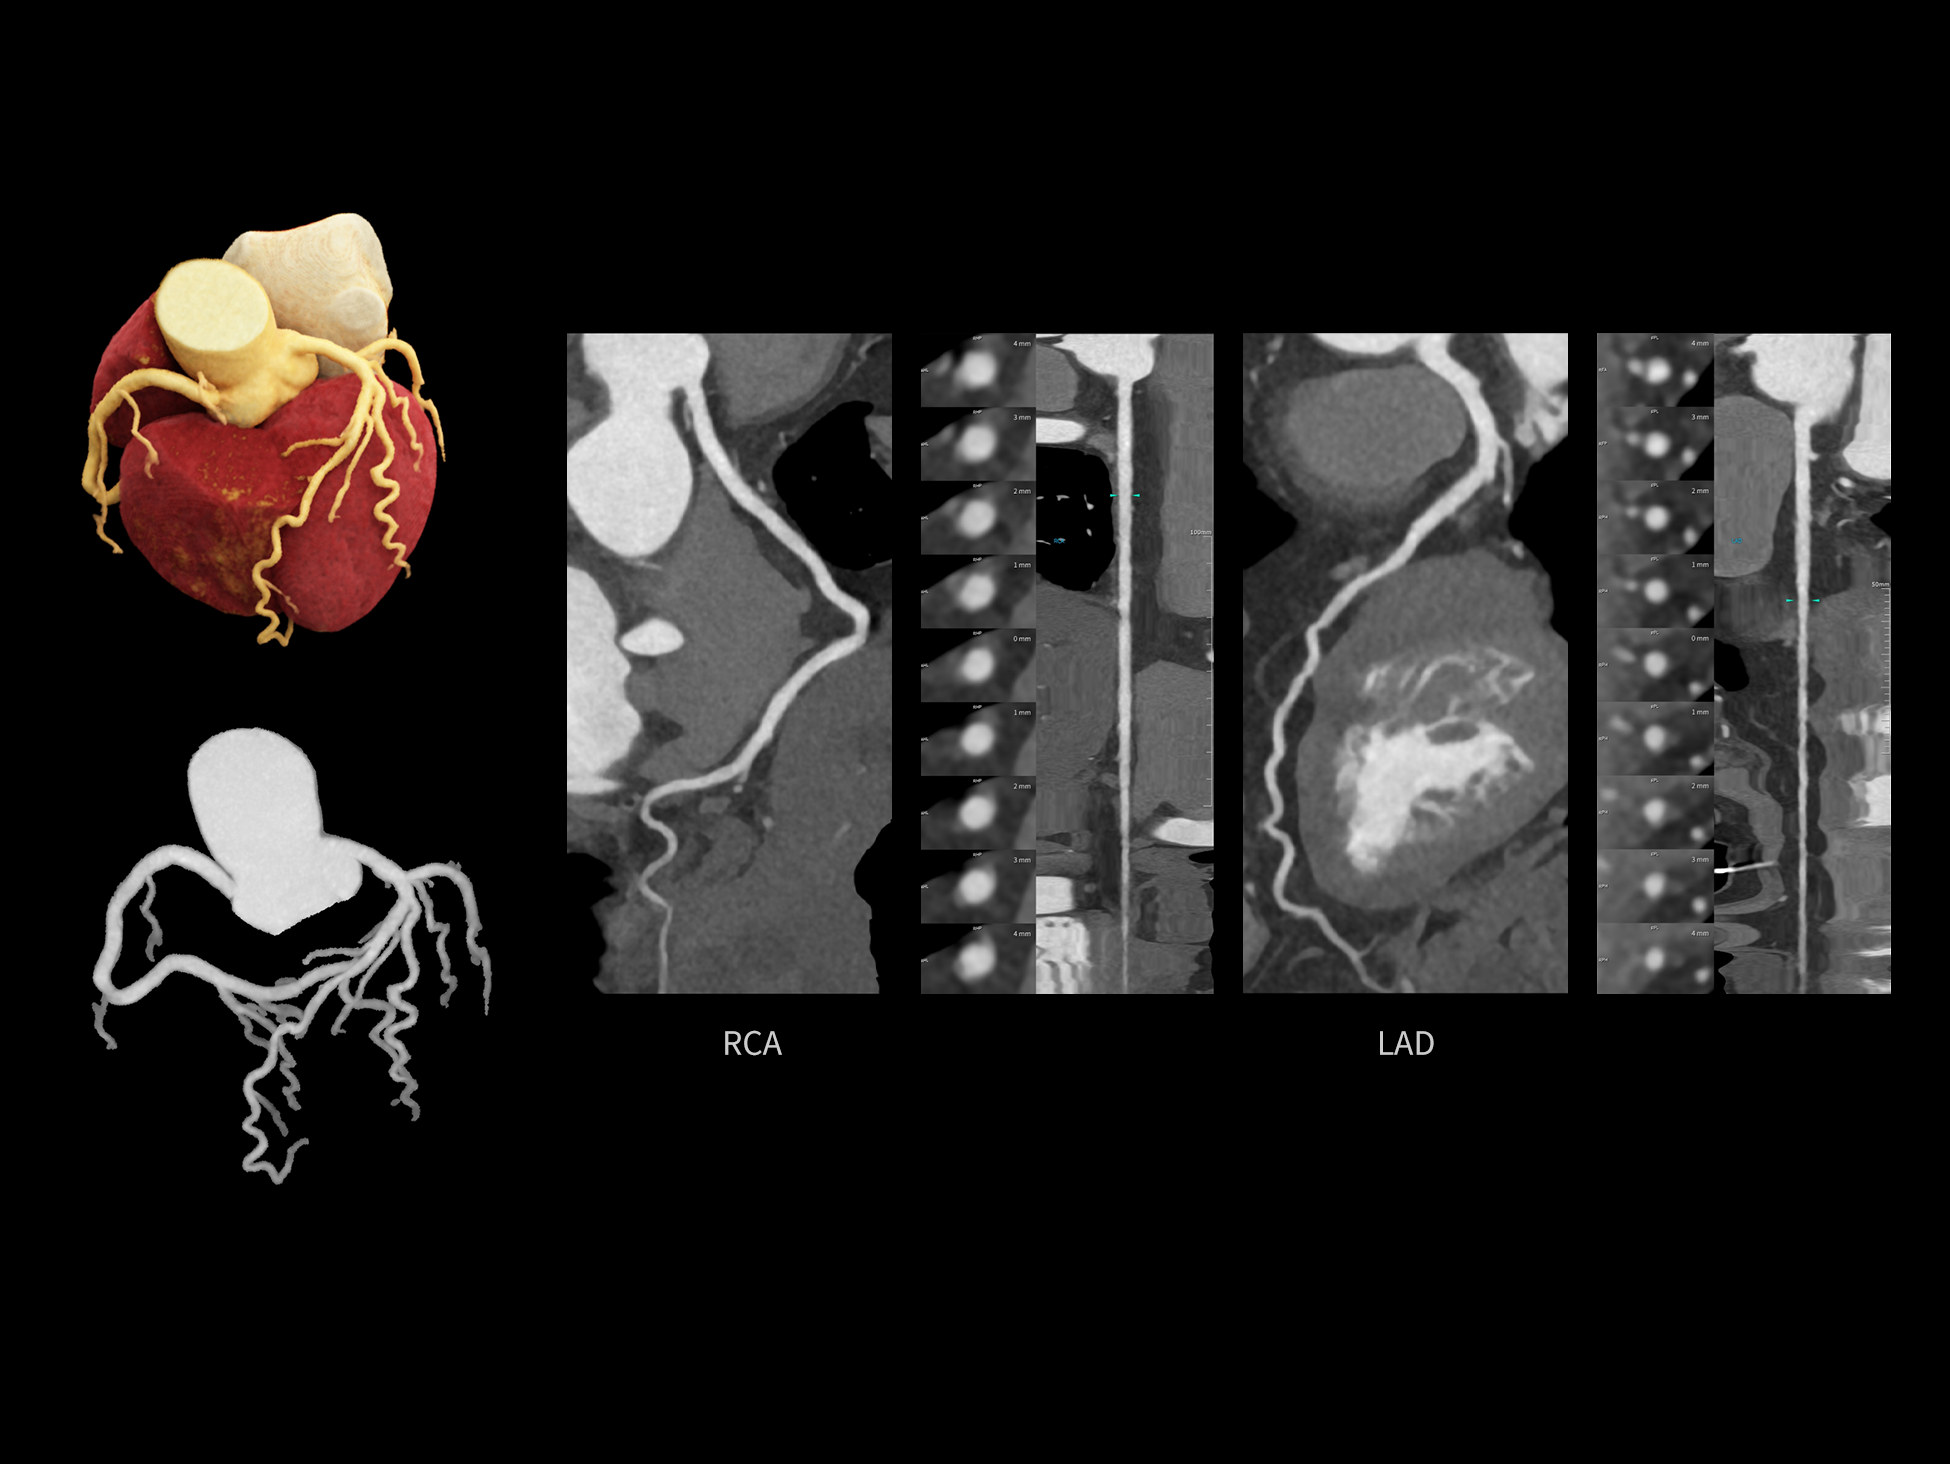

CardioCapture 2.0 通过“识别–追踪–建模–校正”的完整流程,精准分割心脏结构,动态追踪运动轨迹,并构建多时相运动场,最终实现冠脉、瓣膜、心肌及心室结构的同步校正,清晰洞见每一次心跳细微变化,真正将心脏动态掌握于毫秒之间。

CardioCapture 2.0 在目标时相前后重建多时相影像,通过深度学习网络精准提取冠脉中心线,进而建立时相间运动模型,实现对冠脉分段图像的精准运动校正。

冠脉运动校正